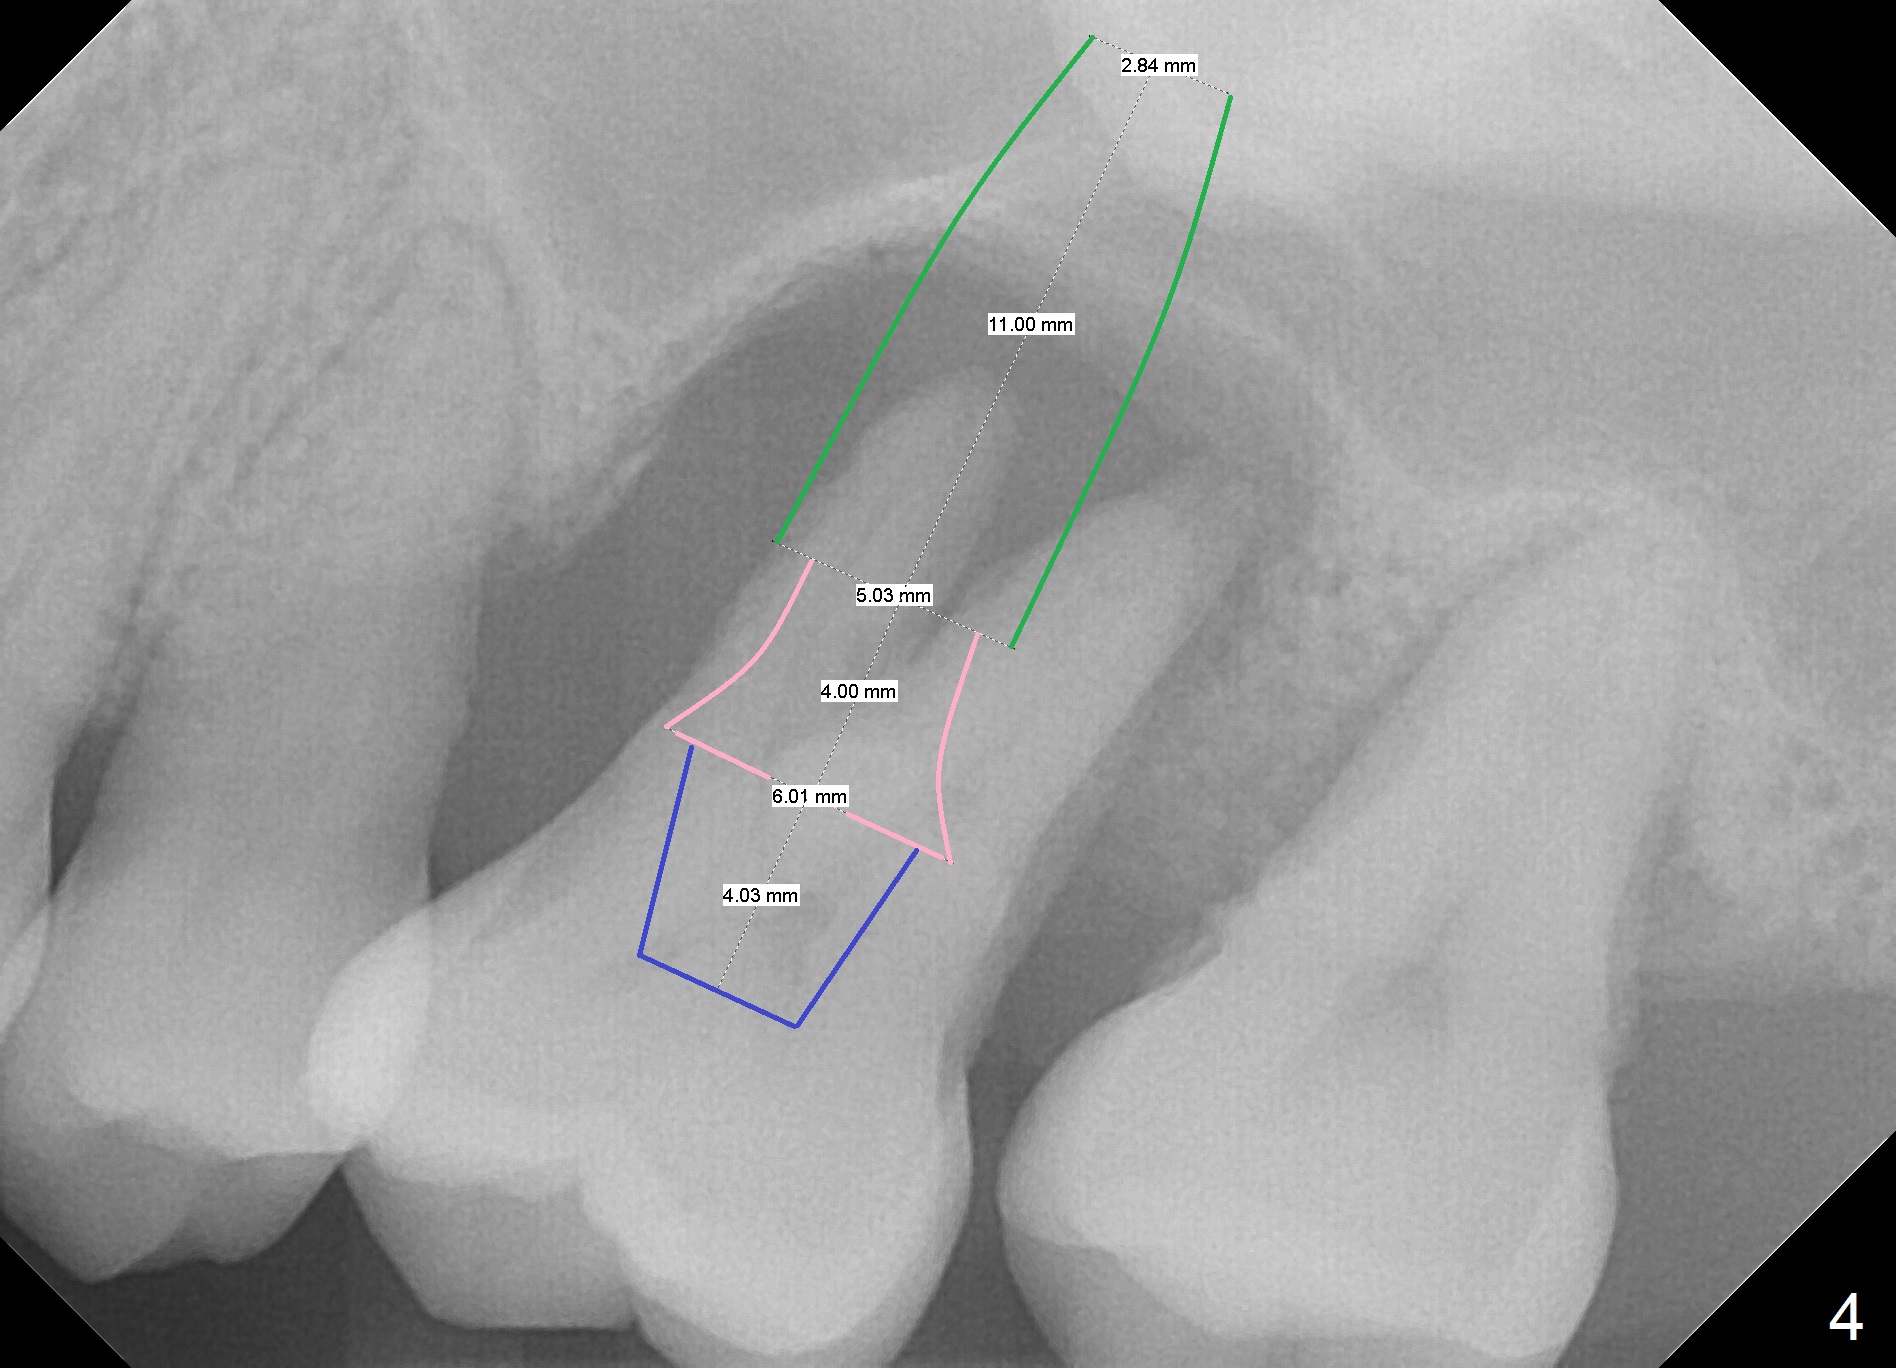

A 41-year-old man has had severe periodontitis at #14 for the last 11 years (Fig.1-3). Finally the tooth is mobile. Draw blood for PRF membrane (x4). After use of Magic Drill with 3 mm stopper, tap Magic Lifter for sinus lift. Insert 1-2 PRF membrane(s) and Vanilla graft prior to further osteotomy with UF drills until 4.5 or 5 mm. Insert tap drill for primary stability. If it fails, switch to IBS dummy implants.

1